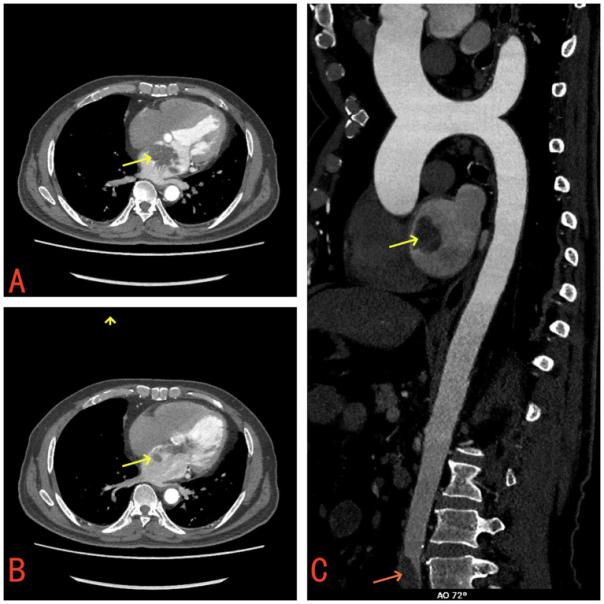

胸部计算机断层扫描(CT)和心电图正常。主动脉和冠状动脉CT血管造影(CTA)显示左心房存在占位性病变,腹主动脉和双侧髂总动脉交叉处存在充盈缺损,提示血栓形成(图1)。

图1 (A) 增强CT显示左心房有肿块(黄色箭头)。(B)左心房大块脱垂通过二尖瓣进入左心室(黄色箭头)。(C)在腹主动脉和双侧髂总动脉分叉处观察到血栓样充盈缺损(红色箭头)